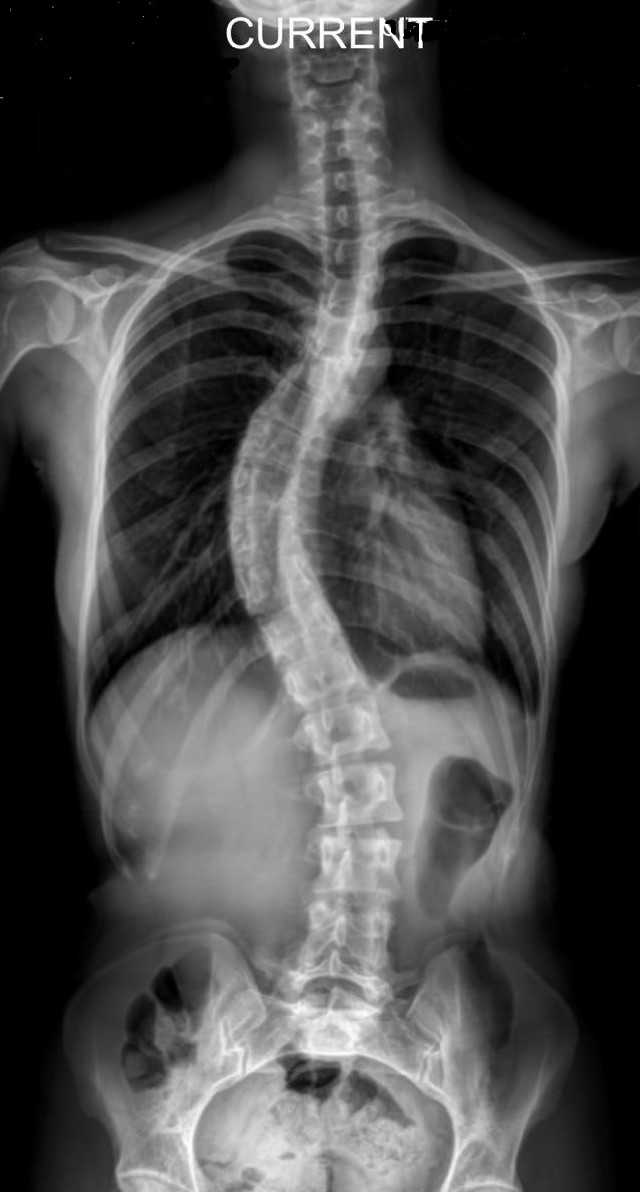

SKOLYOZ HAKKINDA

Skolyoz omurganın ve göğüs kafesinin şeklinde 3 boyutta meydana gelen değişimlerdir. Bir omurgadaki eğriliğin skolyoz olarak adlandırılabilmesi için ön-arka radyografisinde eğriliğin 10 dereceden fazla ölçülmesi beklenmektedir. Skolyoz, fonksiyonel ve yapısal olarak iki grupta ele alınır. Fonksiyonel skolyoz, vücudun herhangi bir bölümündeki bozukluğun kompanse edilmesi için omurgada meydana gelen sapmaların bir sonucudur. Omurganın sağa/sola eğriliği mevcutken, rotasyon görülmez. Eğriliğin yapısı daha esnektir. Bu sebeple öne eğilme testinde (Adam’s testi) eğriliğin düzeldiği görülür. Fonksiyonel skolyozun başta yanlış postüral alışkanlıklar sebebiyle görülmekle birlikte altında yatan başka mekanik durumlar da olabilir. Yapısal skolyozda ise, eğriliğin oluştuğu bölgede kas, eklem, bağ dokusu ve sinir yapılarında yapısal değişiklikler vardır ve omurganın yana kayması ile birlikte omurların birbiri üzerinde döndüğü (rotasyon) de görülür. En fazla dönme eğriliğin merkezinde görülür. Eğrilik sırt bölgesinde olduğu zaman bu rotasyon kaburgaları da etkiler ve yapısını bozarak sırtta ve ön tarafta çıkıntılara neden olur. Bu çıkıntılar ‘gibozite’ olarak adlandırılır. Konjenital skolyoz haricinde diğer skolyoz tipleri fonksiyonel olarak başlayıp zaman içerisinde strüktürel özellikler kazanmaktadır. Yapısal skolyozun; konjenital skolyoz, nöromusküler skolyoz ve idiopatik skolyoz gibi tipleri vardır. Skolyozun tipinin doğru saptanması tedavinin başarısında oldukça önemlidir. Klinikte ve literatürde skolyozun en sık karşılaşılan çeşidi %80 oranla İdiopatik skolyoz olup nedeni hala bilinmemektedir. İdiopatik skolyozun en sık rastlananı ise 9-17 yaş arası görülen Adolesan İdiopatik Skolyozdur (AİS). Cobb açısı 10° ile 20° arasında olduğunda, kız/erkek oranı benzerken, 20° üstündeki eğrilikler kızlarda görülme oranı oldukça artmaktadır. AİS’in ortaya çıkışını ve ilerleyişini açıklamak için birçok teori üretilmiş olsa da kesin bir neden bilinmemektedir. Geçmişte genetik aktarımın üzerinde durulduysa da günümüzde; genetik kaynaklı, mezenkimal kök hücre kaynaklı, doku kaynaklı , omurga biyomekaniği kaynaklı, sinir sistemi kaynaklı, hormon kaynaklı, biyokimyasal kaynaklı, çevresel kaynaklı, yaşam tarzı kaynaklı farklı teoriler bulunmaktadır. Bu potansiyel sebepler kişi bazında kesin olarak saptanamamakla birlikte bu açılardan var olan bozuklukların göz önünde bulundurulması önemlidir. Günümüzde skolyoz,  cerrahi ve cerrahi olmayan yaklaşımlar ile tedavi edilmektedir. AİS tedavisinde son seçenek olarak görülen cerrahi yöntemler, eğriliğin ilerlemesini durdurmak veya eğrilikte düzeltme sağlamak amacıyla ve Cobb açısı 45°’den fazla olan olgularda kullanılmaktadır uygulanmaktadır. Cerrahi olmayan tedavinin temel amaçları, büyüme döneminde eğriliğin ilerlemesini önlemek, cerrahi tedaviyi geciktirmek ya da önlemek, eğriliğin derecesine ve yerine bağlı olarak gelişen solunumsal problemleri önlemek ya da tedavi etmek, özellikle yetişkinlerde görülen spinal ağrı sendromunu önlemek ya da tedavi etmek ve postüral düzeltmeler ile dış görünümü düzeltmek olabilmektedir. Bunların yanında Cobb derecesini azaltmak,  yaşam kalitesini arttırmak, psikolojik iyileştirme de diğer hedefler arasındadır. Bu amaçlar doğrultusunda; gözlem, skolyoza özgü düzeltici egzersizler ve korse yaklaşımları uygulanmaktadır. Ayrıca elektrik stimülasyonu, manipülasyon, mobilizasyon ve tabanlık gibi uygulamalar da tedavide yardımcı bileşenlerdir. Korse uygulaması, kemik gelişimi tamamlanmamış ve Cobb açısının 25°’ nin üstünde olduğu olgular için önerilen, geçerli bir tedavi yöntemidir. Korsenin etkinliği, hastanın korseye olan uyumuna, korsenin düzeltme etkisine ve giyilme süresine (18-23 saat) bağlıdır. Korsenin uygunluğu klinik ve radyolojik olarak mutlaka kontrol edilmeli ve hastanın ihtiyacına göre belirlenen aralıklarla (3-6 ay) düzenli olarak takip edilmelidir. Bu süreçte skolyozlu bireyi takip eden doktor, fizyoterapist, ortez-protez uzmanının ve tedaviye dahil olan başka bir sağlık profesyoneli varsa o kişilerin birlikte iletişim halinde çalışması gerekli ve önemlidir.Skolyozda en önemli nokta mümkün olan en erken evrede yakalanması ve bir an önce tedaviye başlanmasıdır. Yaş ilerleyip yapısal değişiklikler arttıkça ve kişiler esnekliklerini kaybettikçe tedavi seçenekleri ve onlardan alınacak verimler azalmaktadır. Skolyoza özgü düzeltici egzersizler ve korse uygulamaları düzenli ve disiplinli bir şekilde devam ettirildiği sürece klinik alanda kişilere özgü belirlenen hedeflere ulaşmak olasıdır. Bu sebeple ailelerin, öğretmenlerin ve sahadaki sağlık profesyonellerinin özellikle çocuk popülasyonlarda postüral olarak bir takım değişiklikler açısından bilinçli olması önem arz etmektedir. Fark edilebilecek bu postüral değişimler :- Omuz seviyeleri arasındaki fark- Kürek kemiklerinde asimetrik görünüm- Önde asimetrik göğüs kafesi çıkıntısının oluşması- Göğsün bir tarafa kayması, simetrik olmaması- Bel kavislerinde farklılık- Kalçanın bir yana kayması- Bacak boyunun farklı gözükmesi- Öne eğildiğinde vücudun sağ ve sol yarısında yükseklik farkının oluşması gibi durumlardır.Bu maddelerden biri veya birkaçı fark edildiğinde bir uzamana başvurulması gerekmektedir.(Bu yazının hazırlanmasında birçok kitap,makale ve tez kaynaklarından ve klinik deneyimlerden faydalanılmıştır.)